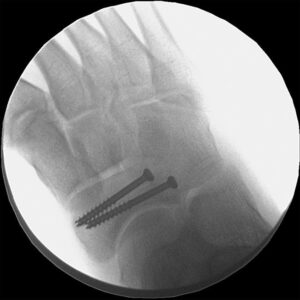

Fractures at the base of the fifth metatarsal, commonly known as Jones fractures, were first identified by Sir Robert Jones. These injuries typically present as pain on the outer midfoot without a clear acute injury and are prevalent among high-level athletes. Healing can be challenging due to the poor blood supply to this region. Non-surgical treatment typically involves immobilization in a cast or boot for at least six weeks, along with supplements like vitamin D or bone stimulators to enhance healing. Athletes may require up to 12 weeks before returning to sports. In some cases, surgery is necessary and may involve screws, bone grafting, or plates. Post-operative adherence to activity restrictions is critical for recovery.